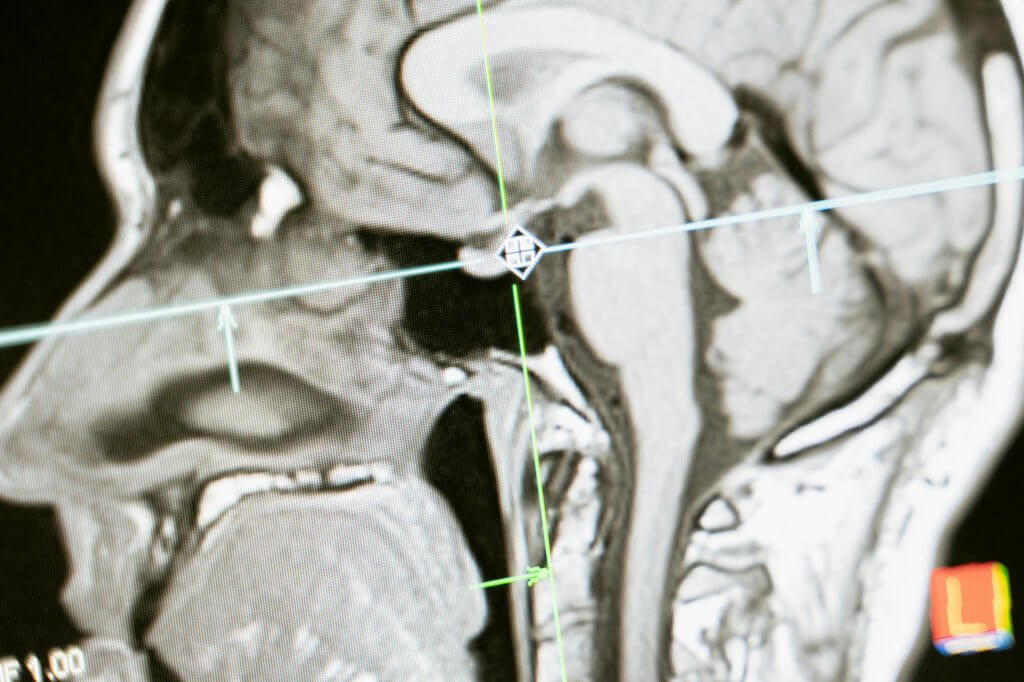

Neuroimaging:

Hippocampal and cortical volume declined in both groups (no significant difference)